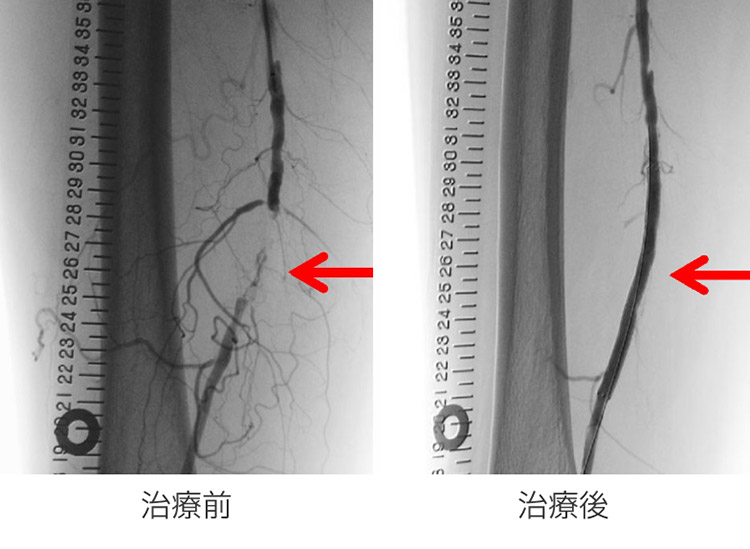

装置の構造が広い可動領域を持つCアーム型となっており、さまざまな角度から透視・撮影を行うことが可能です。当院では主に血管撮影として使用していますが、X線TV検査としても利用できます。

血管撮影検査・治療画像

透析シャントPTA

下肢PTA

※PTA(Percutaneous Transluminal Angioplasty):経皮的血管形成術